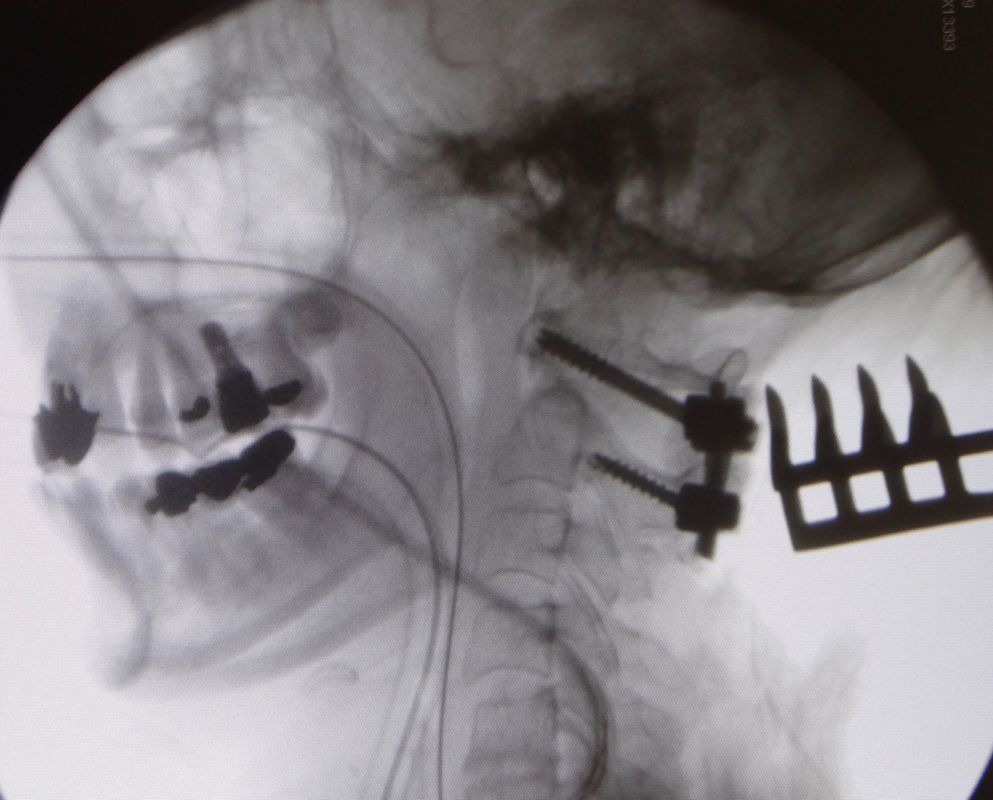

On distingue deux grands types de fracture vertébrale. La première catégorie se caractérise par les fractures traumatiques, qui surviennent lors d’un traumatisme majeur (accident de la voie publique, accident de sport, chute d’une hauteur > 2 mètres,…). La deuxième catégorie se définit par les fractures pathologiques. Ce sont des fractures qui surviennent spontanément ou lors de traumatisme mineur. Il existe toujours une cause sous-jacente à ce type de fracture comme l’ostéoporose, les tumeurs ou les métastases.

Le symptôme principal dans une fracture est la douleur (cervicale, dorsale ou lombaire) intense et survenant directement après le traumatisme. Dans le cas des fractures pathologiques, les douleurs peuvent survenir spontanément ou lors d’un traumatisme mineur. Lorsque la fracture déplace la vertèbre vers l’arrière, il arrive que les structures nerveuses (moelle épinière ou nerfs) soient comprimées, et des troubles dits neurologiques apparaissent, tels que l’engourdissement, les fourmillements, une faiblesse, voire même une paralysie.

Les fractures peuvent survenir n’importe où dans la colonne vertébrale, mais touche plus particulièrement les vertèbres dorsales et lombaires.

Le traitement va dépendre du type de fracture et de l’atteinte neurologique. Il va du traitement conservateur par corset ou minerve à la fixation par des vis avec parfois une résection de la vertèbre fracturée et le placement d’une cage en titane. Parfois, une injection de ciment (cyphoplastie) suffit à stabiliser la fracture.

Les tumeurs apparaissant dans la colonne vertébrale sont le plus souvent des métastases d’un cancer primaire (cancer du sein, de la prostate, des poumons, des reins,…). Ce sont des lésions qui se développent à distance du cancer primaire. Elles touchent la colonne dorsale et lombaire le plus souvent et parfois la colonne cervicale.

Certaines tumeurs ont leur origine dans les structures mêmes de la colonne vertébrale (os, moelle épinière, nerfs/racines nerveuses). On parle, alors, de tumeurs primaires.

Les symptômes sont en premier lieu la douleur localisée au niveau de la tumeur. Le reste des symptômes surviennent si la tumeur comprime des structures nerveuses, telles que la moelle épinière ou des nerfs. Dans ce cas-là, des troubles sensitifs ou moteurs sous forme d’engourdissement, perte de sensibilité et faiblesse, voire paralysie apparaissent progressivement. Une incontinence urinaire ou fécale (perte des urines ou des selles involontaires) peut également s’installer. Des troubles de la marche ou de l’équilibre sont aussi fréquents. Les tumeurs provoquent des fractures que l’on nomme pathologique, en raison de l’affaiblissement de la structure osseuse par la tumeur.

La prise en charge rapide, une fois le diagnostic établi, est essentielle pour maintenir la qualité de vie du patient. Le traitement est une prise en charge pluridisciplinaire faisant intervenir des neurochirurgiens, oncologues, radiothérapeutes, radiologues et pathologistes.

Le but du traitement chirurgical est de stabiliser la colonne vertébrale par une fixation, décomprimer les structures nerveuses, obtenir un diagnostic histologique précis, permettre un contrôle tumoral et soulager les douleurs.